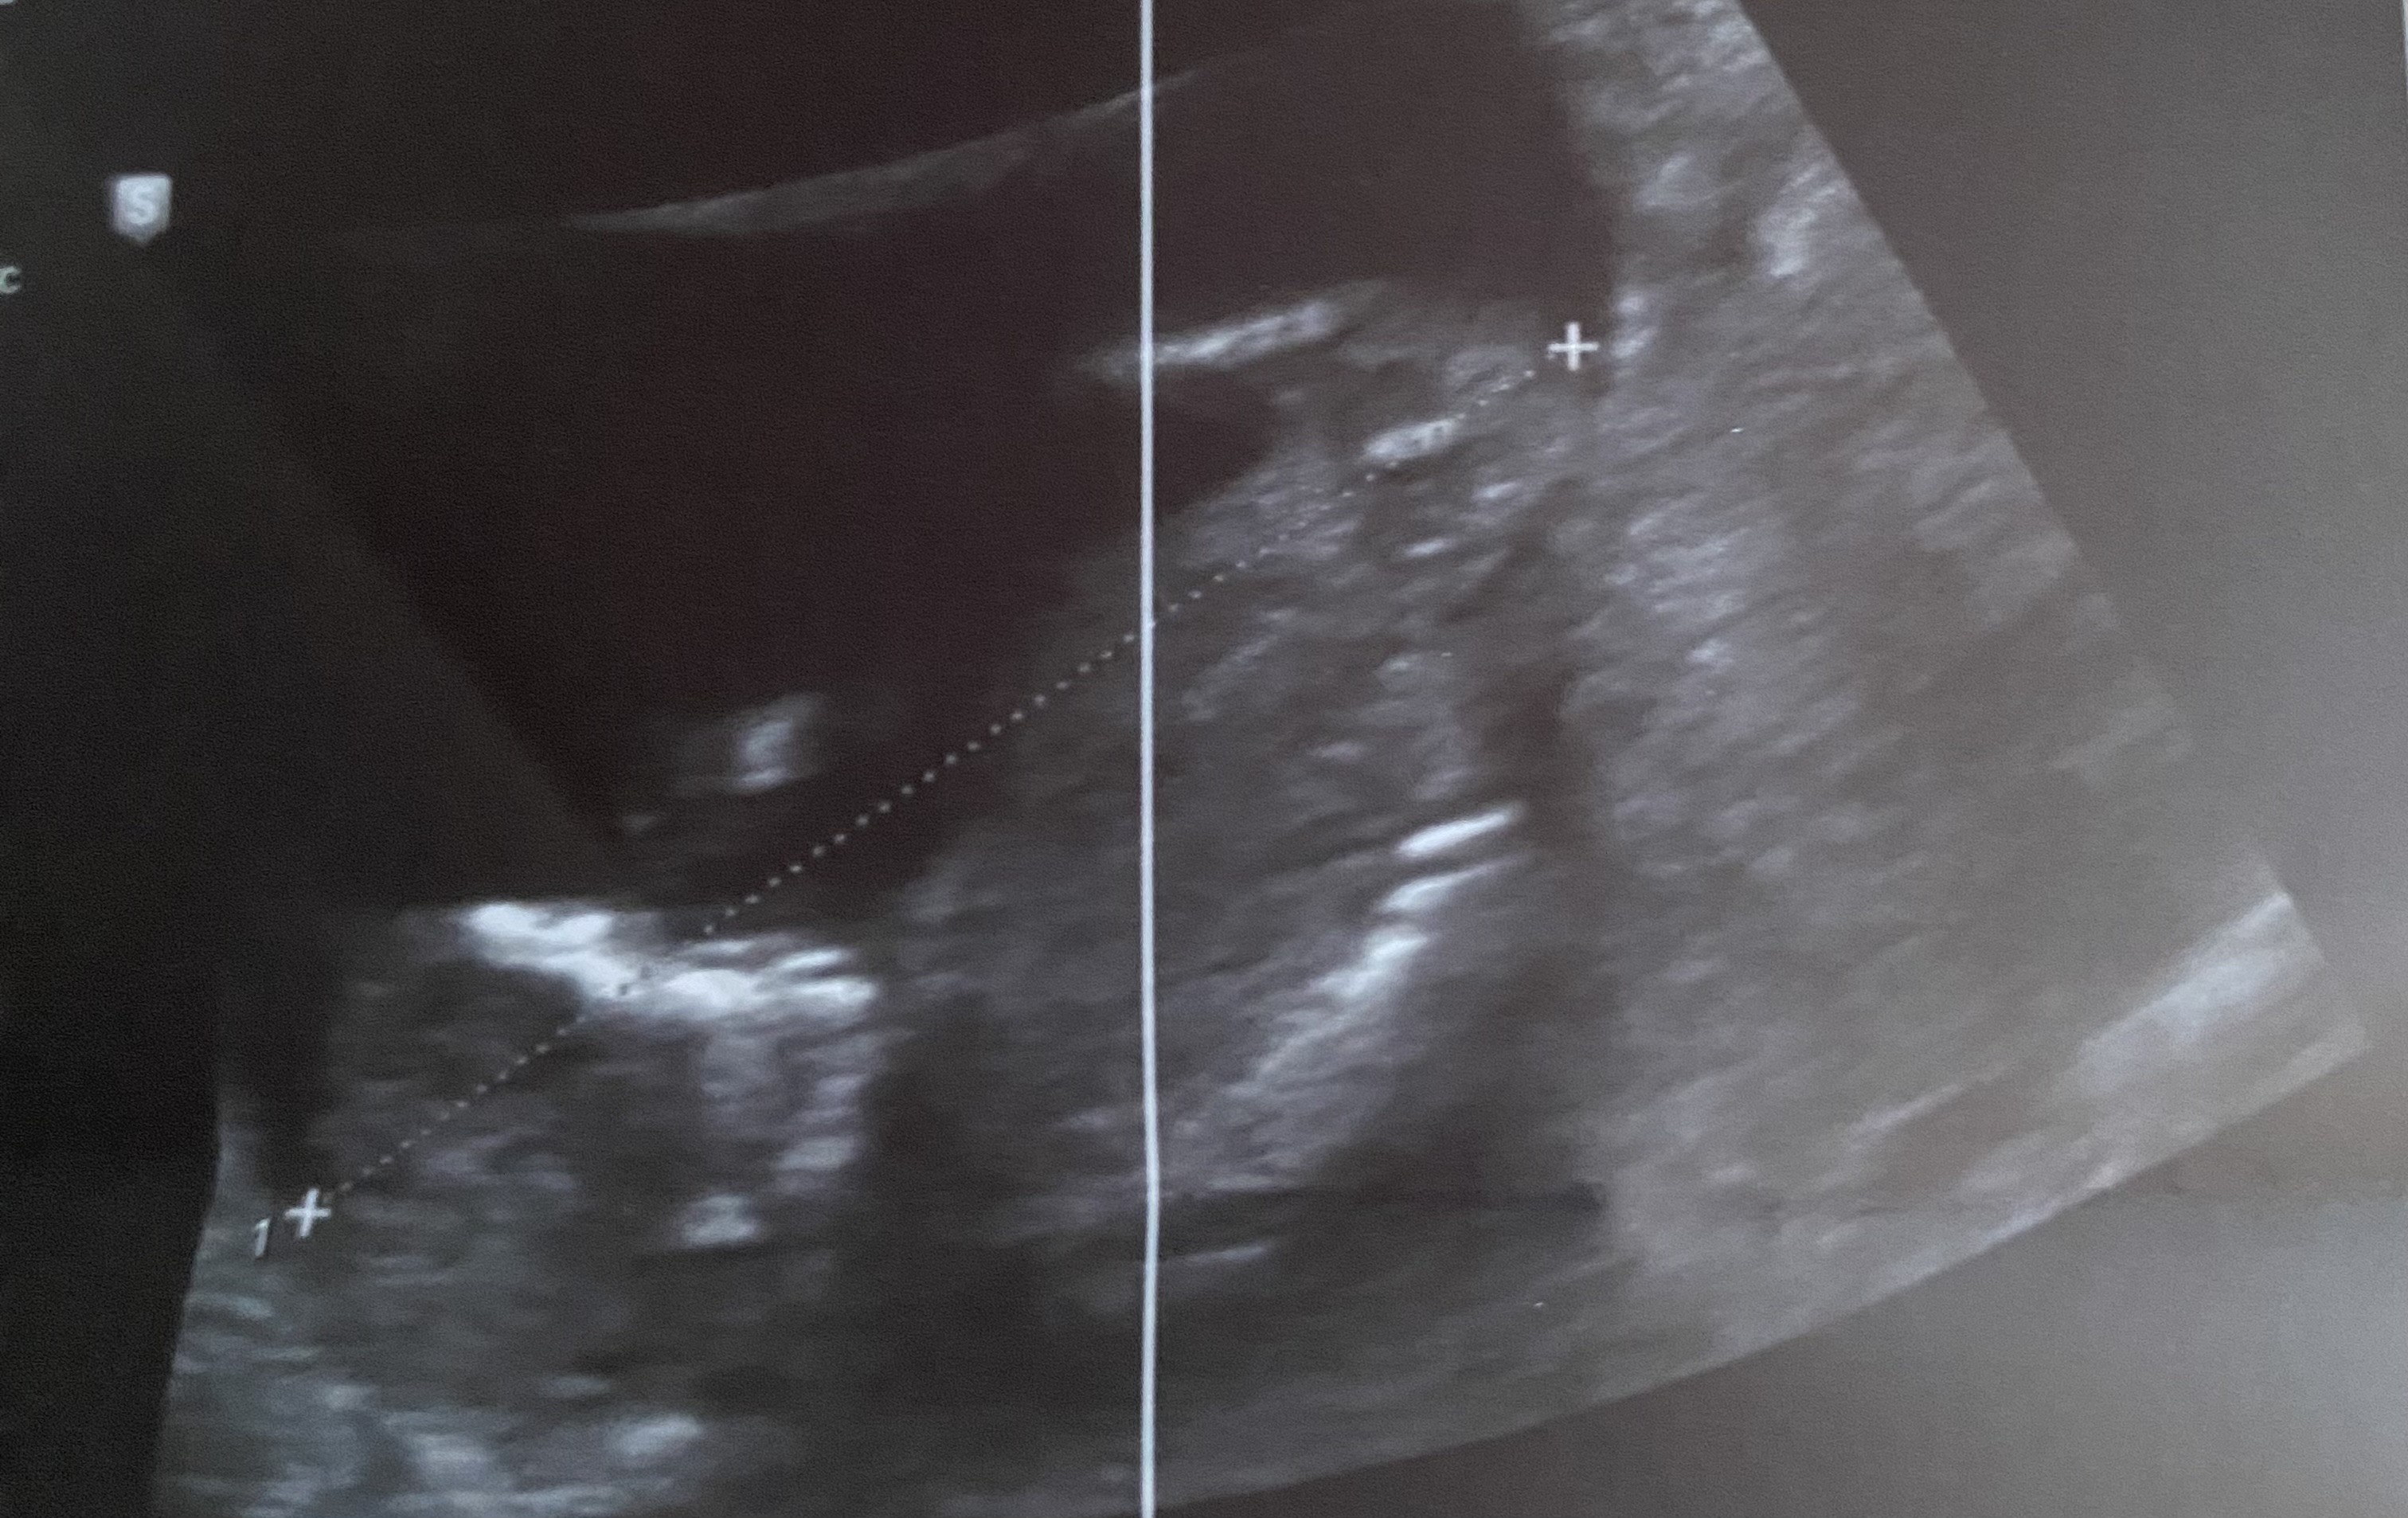

Hej kochane. Czy ktoś zagląda tutaj? I mógłby coś powiedzieć wg tych zdjęć 🙂

• 20241112_174040.jpg

20241112_174040.jpg

953,5 KB · Wyświetleń: 310

• 20241112_174014.jpg

20241112_174014.jpg

904,6 KB · Wyświetleń: 297

• 20241112_174011.jpg

20241112_174011.jpg

1,4 MB · Wyświetleń: 288